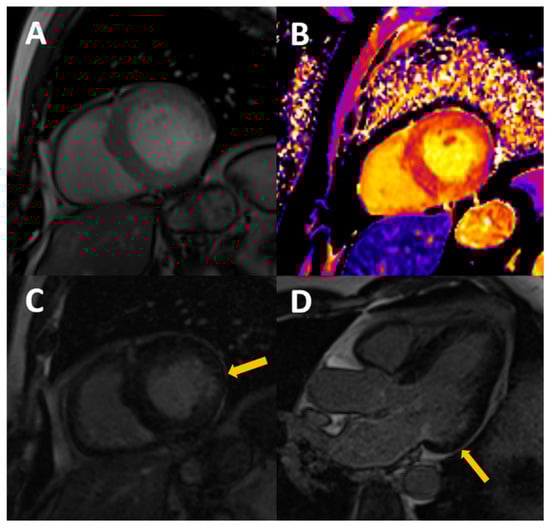

Figure 2.

54-year-old male, with stage III CKD secondary to nefroangiosclerosis, who presents with CMR concentric LVH in cine images (A), mildly increased native T1 (B) with normal T2, probably reflecting appropriate volume status with some degree of diffuse fibrosis. A previously unknown myocardial infarction is present as a subendocardial scar in mid-basal segments of the inferolateral wall (arrows in C,D).